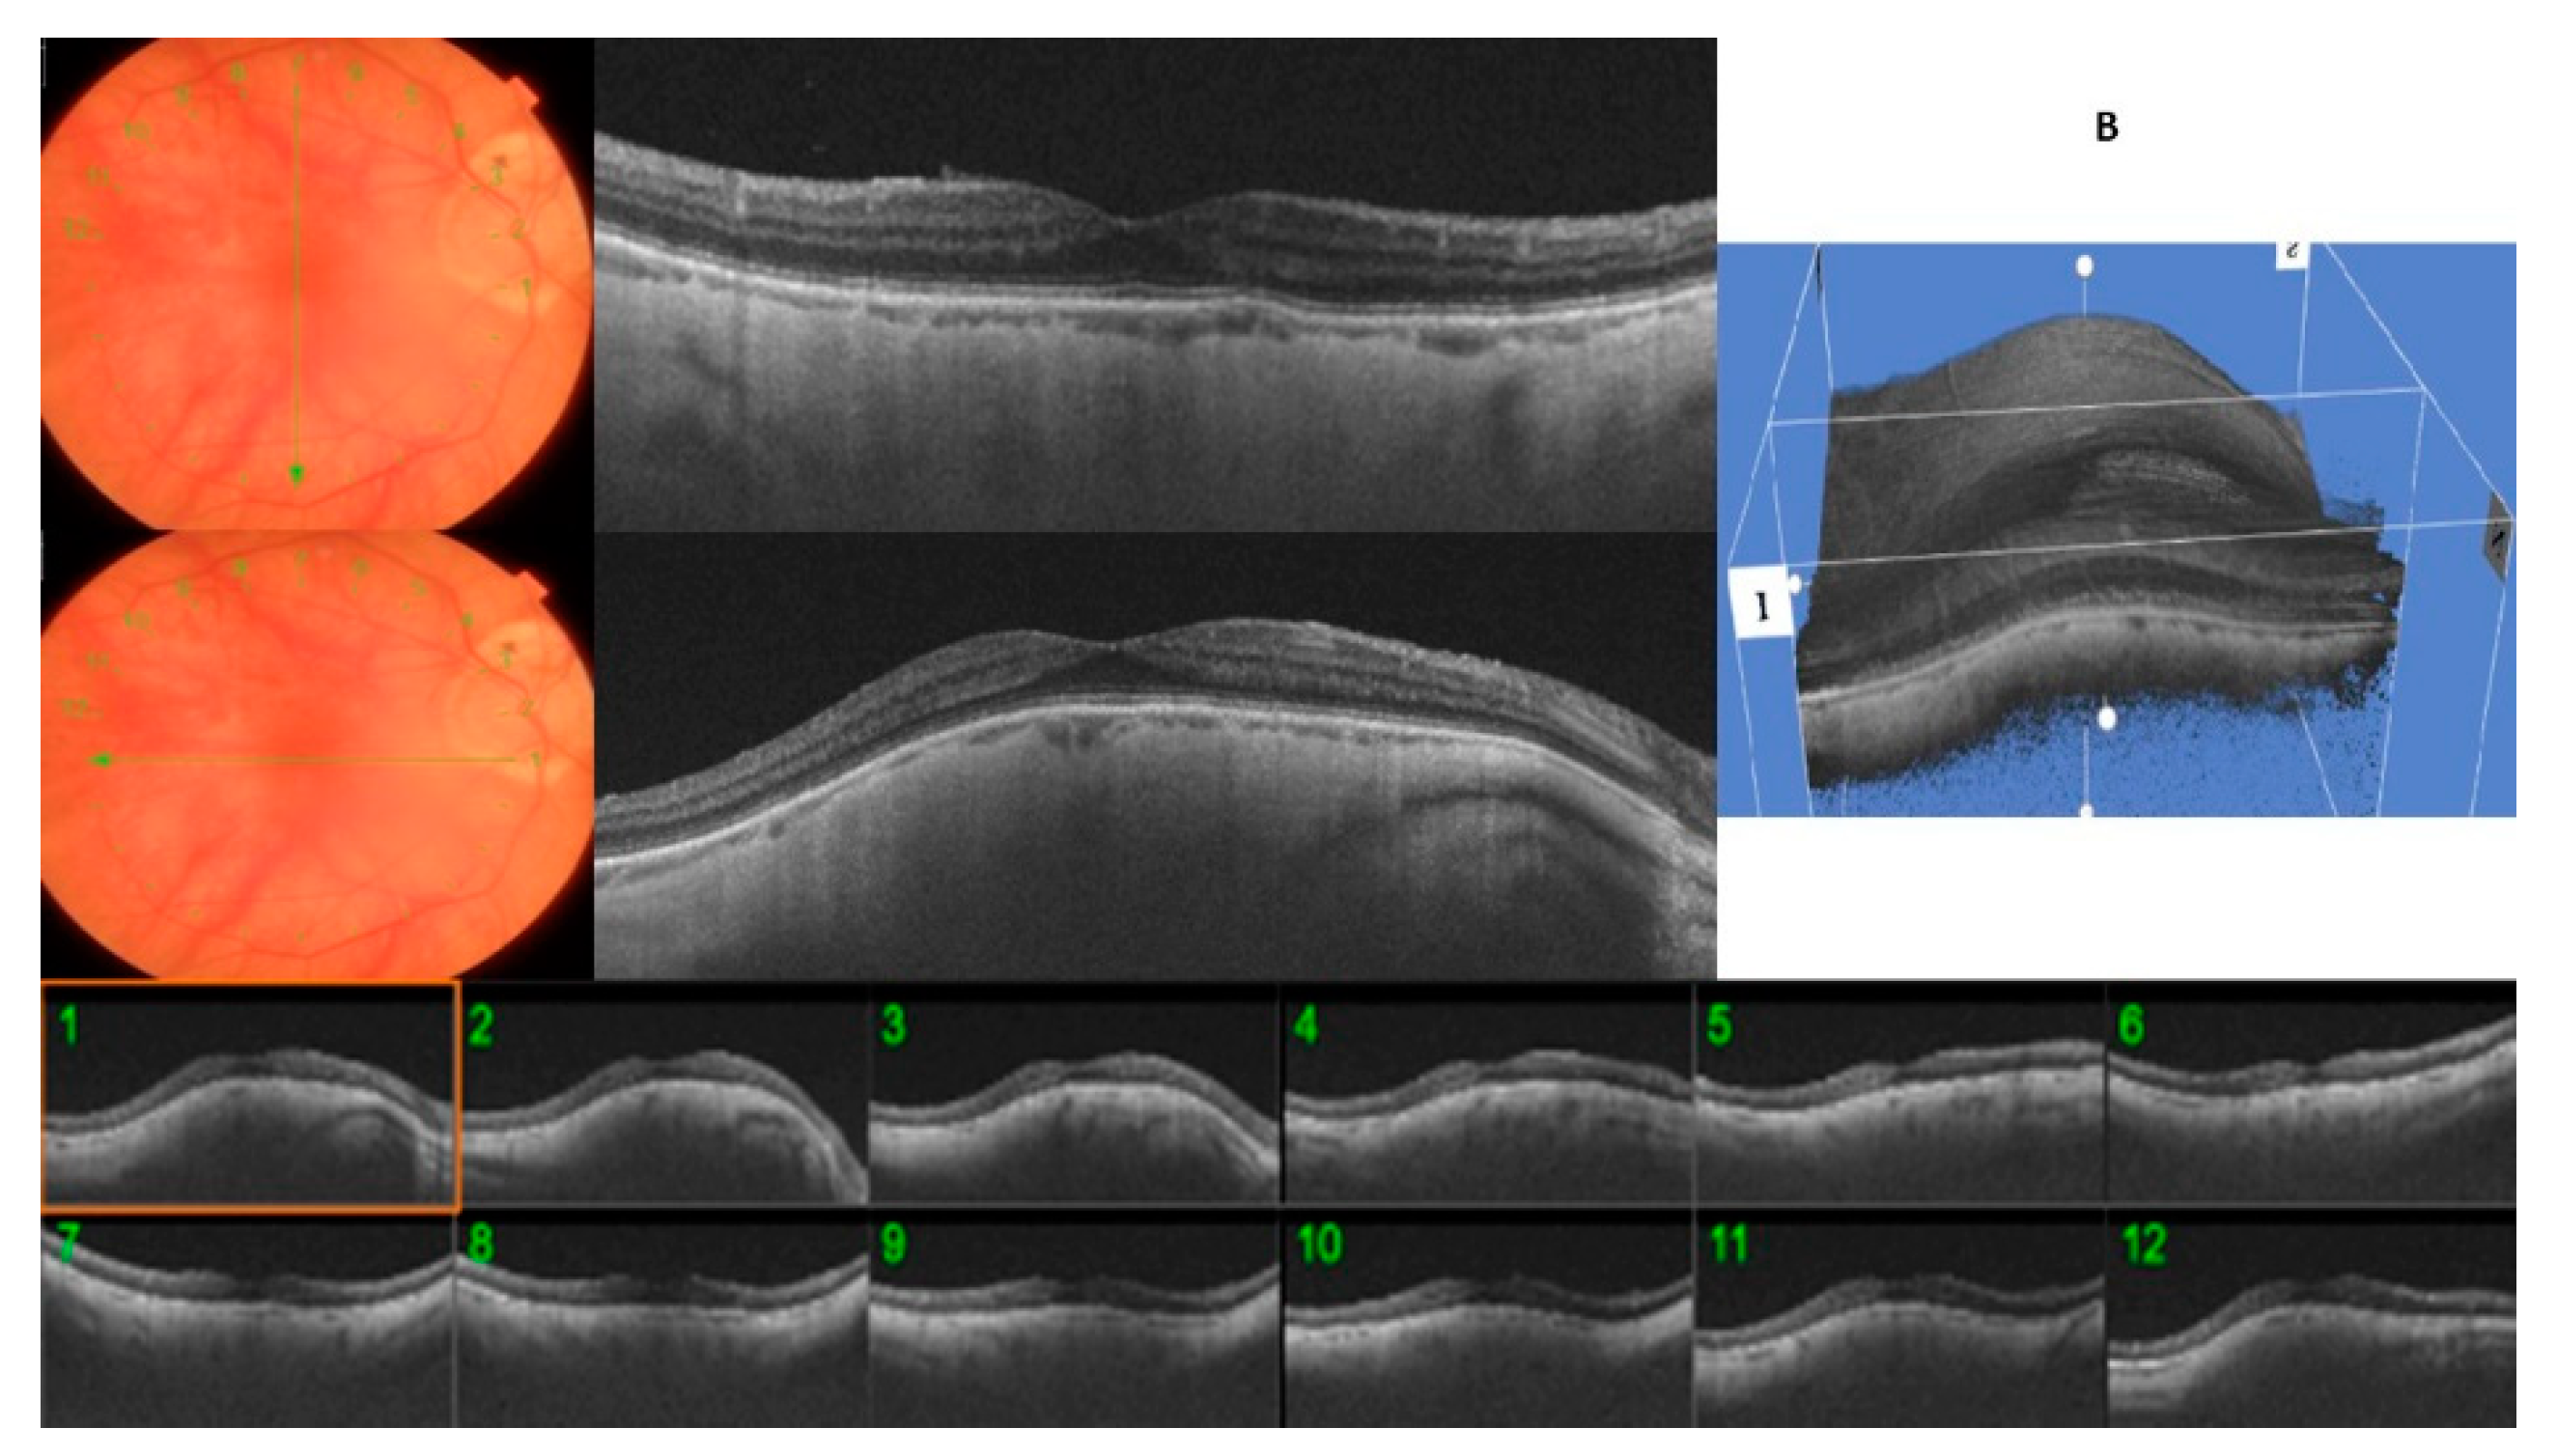

A typical round dome-shaped macula, with the 12 radial OCT scans centered on the fovea showing an elevation of ≥50 µm, was found in 12 eyes (24.4%), defining the DSM group (Figure 2). However, despite being round, all of them presented a predominant orientation, with some scans displaying a higher bulge than the opposing scans. Nine eyes of the DSM group showed a predominant horizontal orientation (75%) versus three eyes that showed a higher bulge in the vertical orientation (25%).

In the RSM group, we included those 37 eyes (75.6%) with <12 OCT radial scans affected. The mean of the OCT scans that showed an inward elevation ≥50 µm was 5.75 ± 1.69. Twenty-six eyes (70.2%) showed only an inward convexity in the horizontal direction manifested across the vertical OCT radial scans, whereas the opposite scans were flat, being classified as horizontally oriented RSM (Figure 3A). Ten (27.0%) eyes showed this inward convexity only in the vertical direction across the horizontal OCT radial scans, fulfilling the definition of a vertically oriented RSM (Figure 3B). One eye (2.7%) was classified as obliquely oriented RSM. The inward convexity occurred bilaterally in 17 eyes (34.6%). In four patients (8.1%), one eye showed the typical round dome-shaped convexity and the other eye showed a ridge-shaped band.

Figure 3. (A)/(B): A ridge-shaped macula (RSM) with six radial OCT scans centered on the fovea showing an inward convexity of ≥50 µm, whereas the macular curvature was unremarkable on opposite perpendicular meridians. (A): horizontally oriented RSM. (B): vertically oriented RSM.